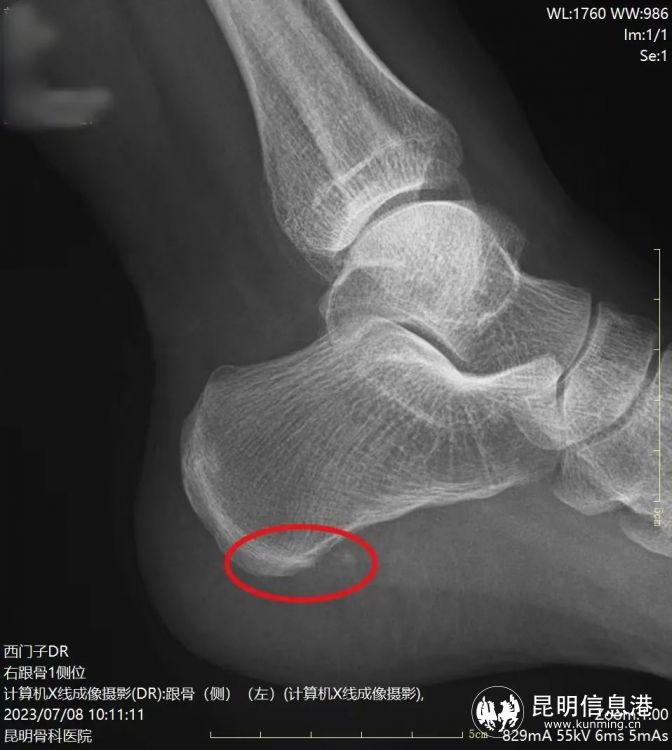

術(shù)前骨刺明顯

術(shù)后骨刺消失

“經(jīng)檢查發(fā)現(xiàn)劉女士不僅左足跟有跟骨骨刺,雙足還有足底筋膜炎,本次微創(chuàng)手術(shù)只需在患者足內(nèi)側(cè)跟骨前結(jié)節(jié)處兩側(cè)各取一個(gè)0.2-0.5cm的小孔,建立鏡下手術(shù)工作通道,就能在可視下磨除跟骨骨刺,筋膜松解,處理炎癥組織?!崩ッ鞴强漆t(yī)院手足顯微外科主任李海波介紹說,這種新型的微創(chuàng)治療手段對比起傳統(tǒng)的治療來講有很大的優(yōu)勢,微創(chuàng)損傷小、恢復(fù)快、手術(shù)疼痛輕等特點(diǎn),傳統(tǒng)的跟痛癥手術(shù)通常從跟骨內(nèi)側(cè)長斜形切口,長約5厘米,典型的“小手術(shù)、大切口”。